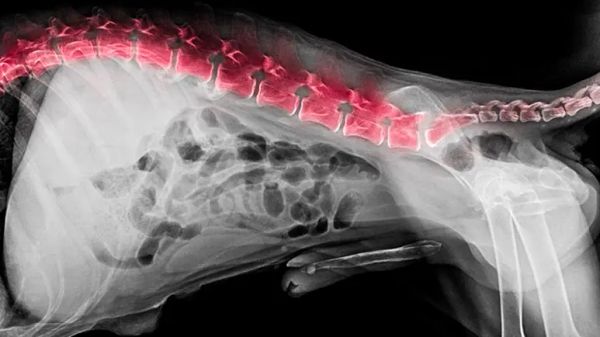

This Allergy Can Make Your Dog Downright Miserable — And May Horrify You

The fact of the matter is that most people never imagine a dog could have this allergy. So it's often undiagnosed, while your dog suffers unbelievable misery. Similarly, pet guardians are totally stupefied to hear this alarming news. Peek inside to find out why.